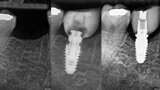

Implant restoration with CEREC